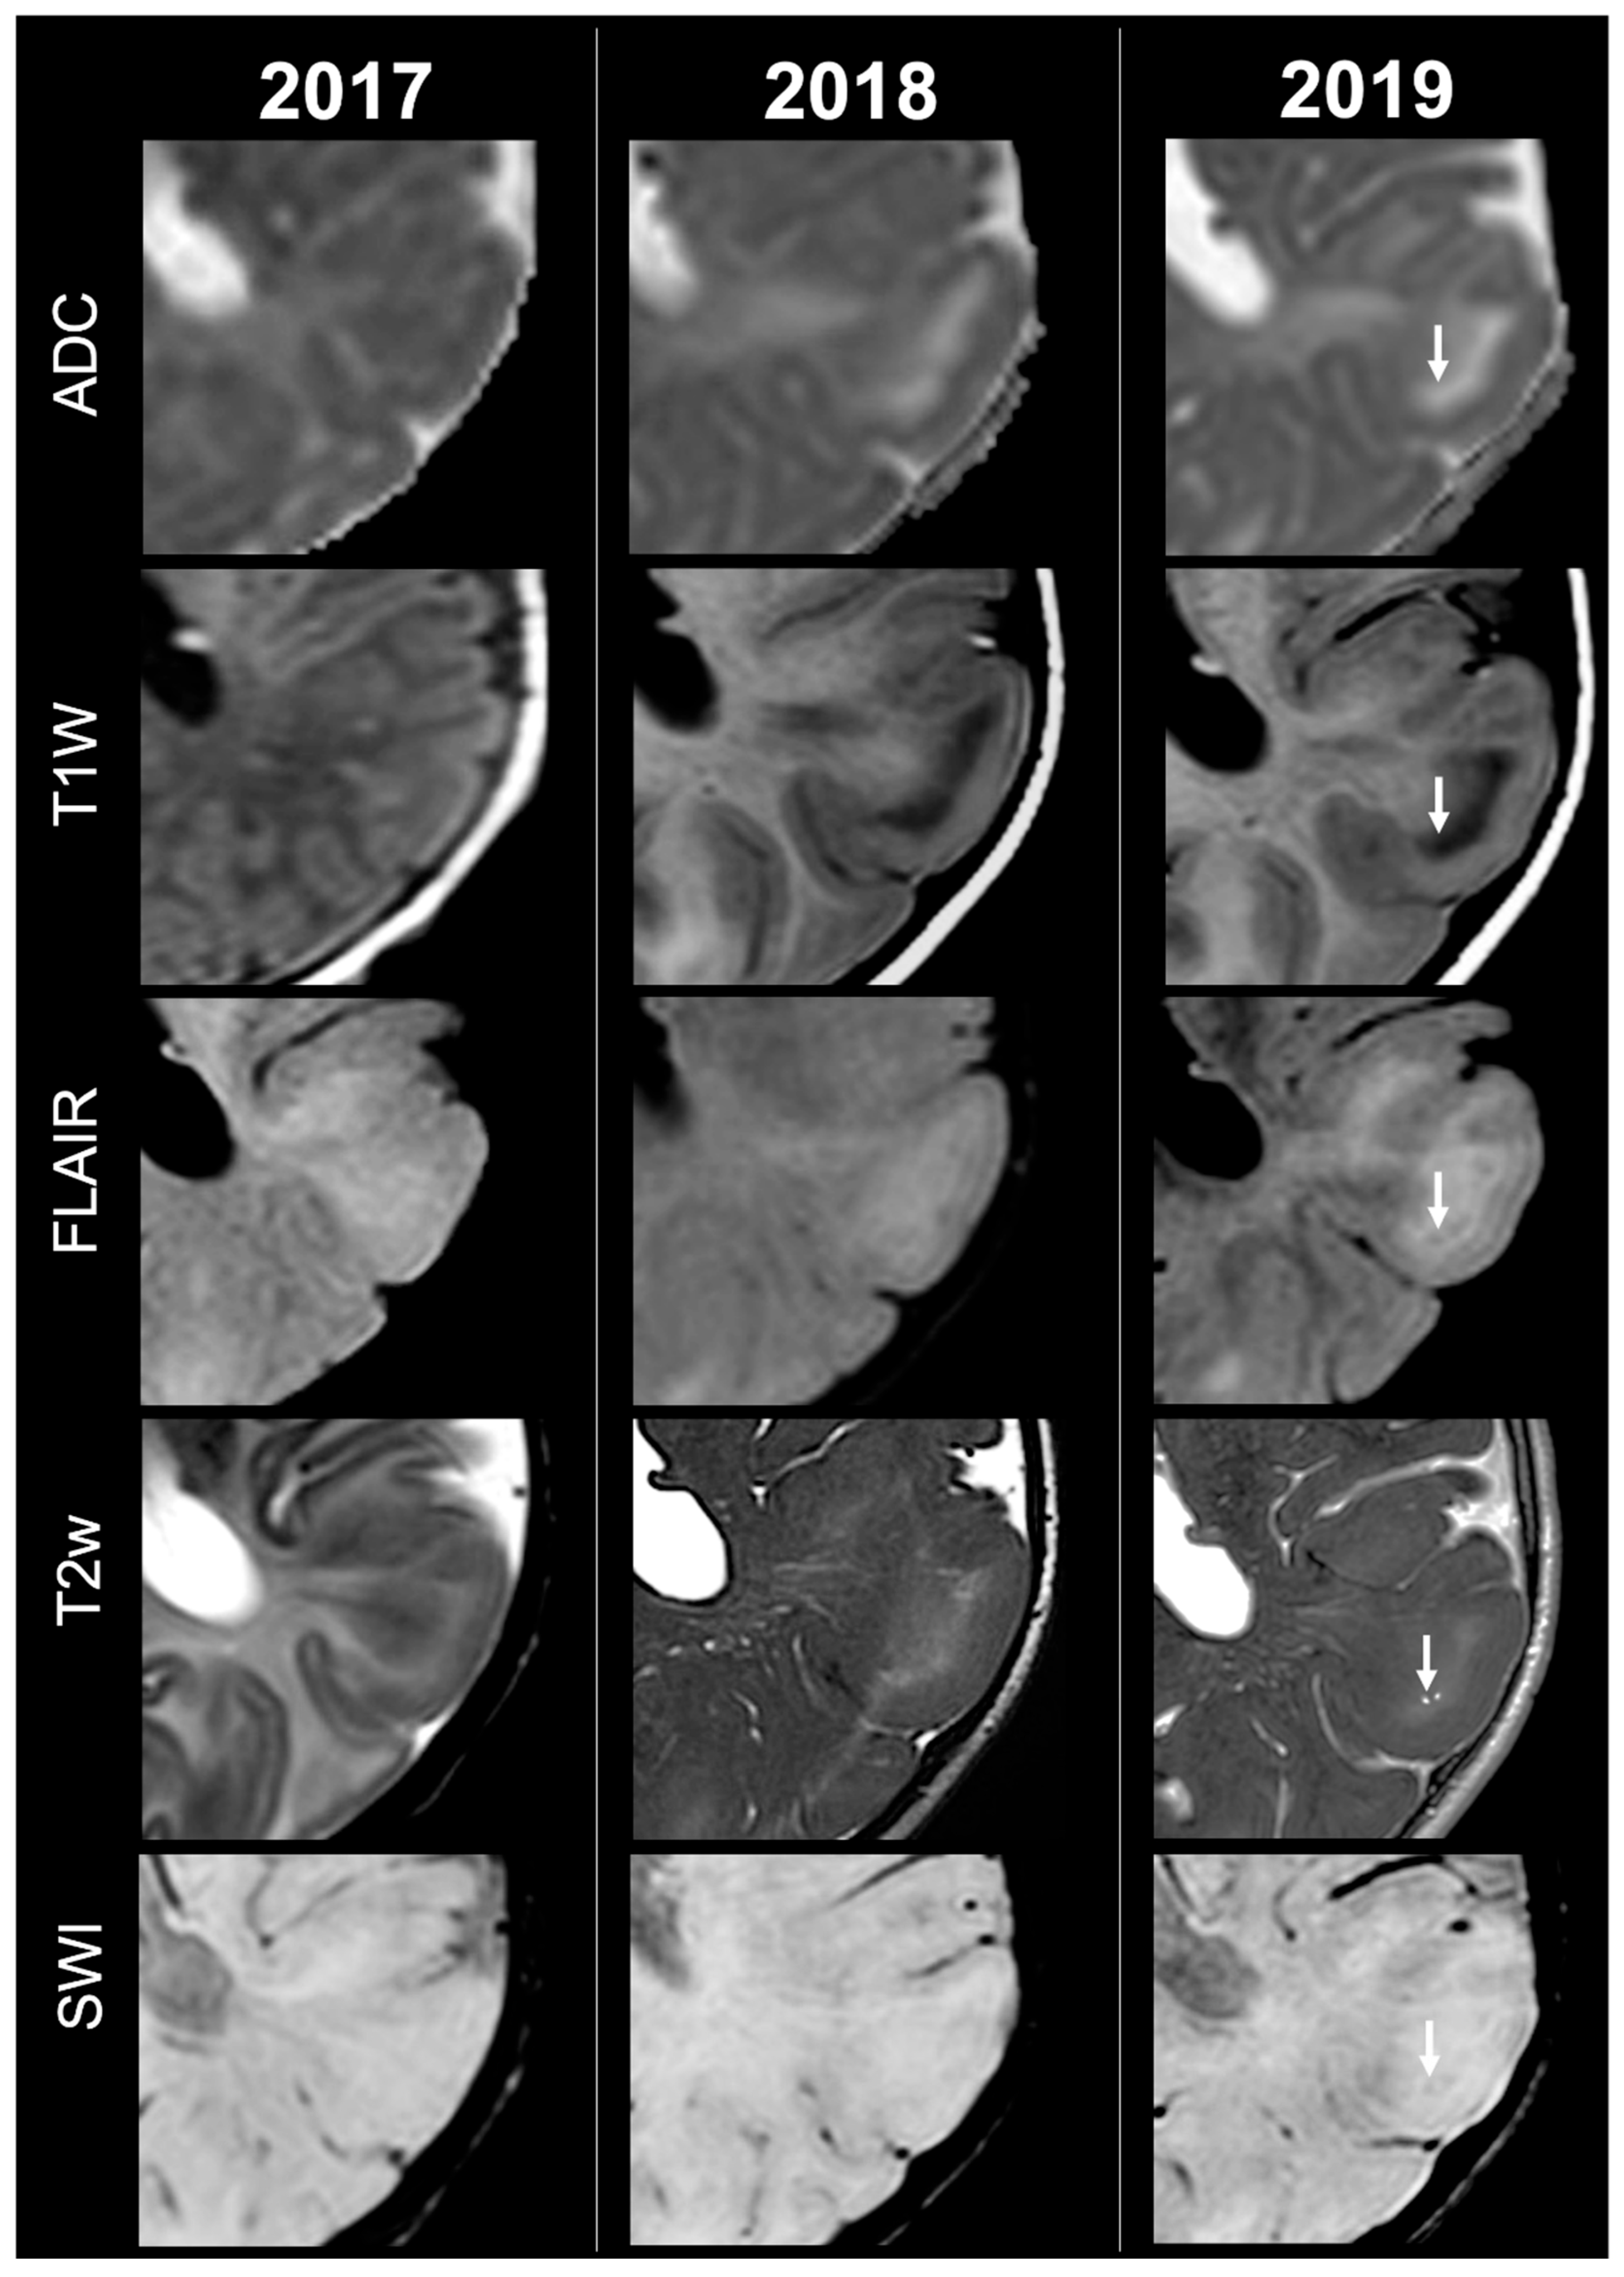

Concerning total lesion count, the interobserver agreement was excellent, with an ICC of 0.91 (95% CI: 0.87–0.95). At baseline, the total number of CTs identified across the cohort was 918 (mean ± SD = 16.1 ± 12.4), whereas at the last available MRI follow-up, the overall count increased to 1070 (mean ± SD = 18.8 ± 13.3), corresponding to a net gain of 152 CTs, equal to a relative variation of +17%. When stratified by tuber type, distinct trajectories were observed over time. Type A CTs, which were relatively abundant at diagnosis (N = 303, mean ± SD = 5.3 ± 7.0), decreased to 255 (mean ± SD = 4.5 ± 5.9) at follow-up, yielding a reduction of 48 lesions (−16%). Conversely, type B CTs showed an opposite trend, increasing from 438 (mean ± SD = 7.7 ± 8.4) at baseline to 556 (mean ± SD = 9.8 ± 8.6) at follow-up, corresponding to a net increase of 118 tubers (+27%). An example of MRI signal evolution from tuber A to tuber B is shown in Figure 1. Similarly, type C1 CTs rose from 160 (mean ± SD = 2.8 ± 4.8) to 220 (mean ± SD = 3.9 ± 5.8), with a net gain of 60 tubers (+38%). Type C2 CTs, initially rare at diagnosis (N = 14, mean ± SD = 0.2 ± 0.8), markedly expanded to 33 (mean ± SD = 0.6 ± 1.5), accounting for an increase of 19 CTs (+136%). Finally, type D CTs were only sporadically encountered, with a modest increase from 3 (mean ± SD = 0.1 ± 0.3) to 6 (mean ± SD = 0.1 ± 0.4), equating to a 100% variation. The observed increment of type C2 tubers was attributable almost exclusively to the progressive transformation of pre-existing type B lesions and, more prominently, type C1 lesions, while the increase in type C1 tubers reflected the gradual conversion of both type A and type B CTs that were already detectable at disease onset. An example of MRI signal evolution from tuber B to C1 is shown in Figure 2, while from tuber C1 to C2 in Figure 3. Only in one patient was a type C1 tuber newly identified at follow-up without clear evidence at baseline. In contrast, newly apparent tubers emerging over time but not clearly visible on baseline scans were most frequently represented by type A and type B lesions. Type D tubers were rare overall and were identified in only six lesions from four patients with a particularly high lesion burden; in all but one case they represented the evolution of type A or type B CTs (an example of MRI signal evolution from tuber A to tuber D is shown in Figure 4), while in a single case they were associated with adjacent subtle calcific foci. Overall descriptive data are summarized in Table 1.

Figure 2.

Right temporal tuber transition from type B to C1 at three different timepoints in a male patient diagnosed with TSC2.